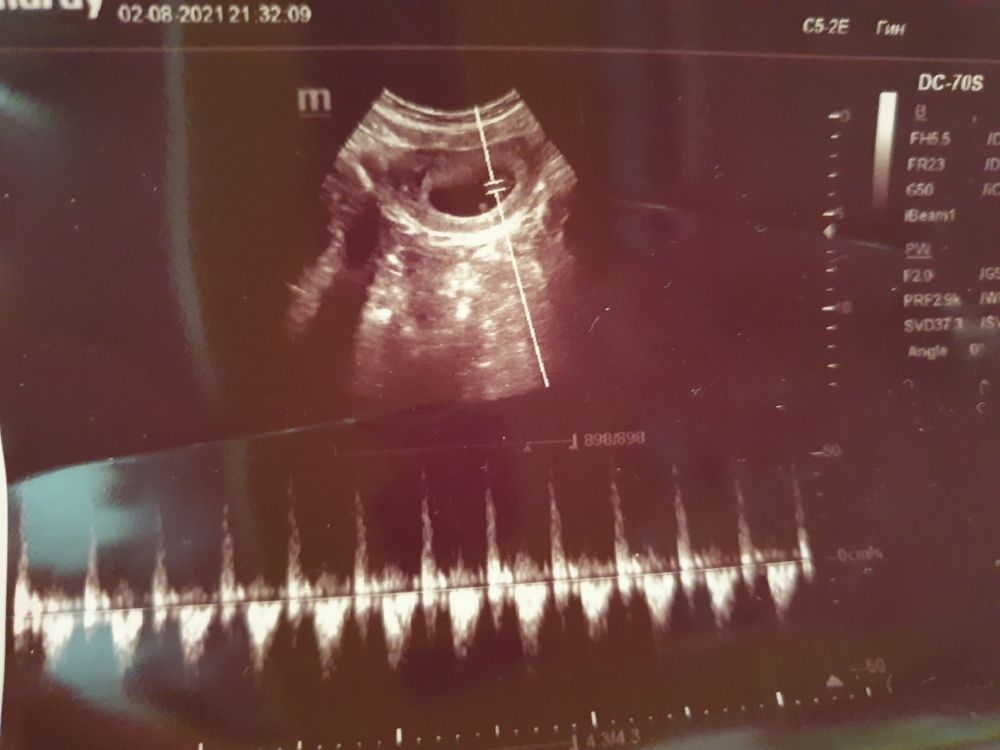

Срок 6-7 недель, кто разбирается в этом методе? Узи трансвагинально, жду предположений ☺️

Срок 6-7 недель, кто разбирается в этом методе? Узи трансвагинально, жду предположений ☺️

Юлия *, Юль, ты, как профи, скажи мне, по какой здесь стороне?))) Я вижу хорион по кругу😊

Юлия Sonnце, скажешь тоже, профи 😂😂😂😂 Я любитель. А хорион вот

Юлия *, но разве это всё по кругу - не хорион?) Я просто иногда чётко вижу справа/слева, а иногда вот кольцом, как, видимо, оно и есть на самом деле. Либо так это передается через датчик УЗИ. Как там мистер Рамзи рассматривал - вот интересно))))

Юлия *, а у меня вот у мальчика так было, как на фото автора. Утолщение левее😊 Фигзнает. Гадание на кофейной гуще и то точнее😆 Лучше, как я говорю, тест на пол сдать или узи в 12 недель дождаться.